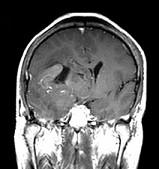

问题 男,55岁,头胀感1年余,头痛3日,请根据所提供图像,选择最可能的诊断()

选项 A.(右额颞)病毒性脑炎 B.(右额颞)星形细胞瘤 C.(右额颞)淋巴瘤 D.(右额颞)少突胶质细胞瘤 E.(右额颞)胶质母细胞瘤

答案 D